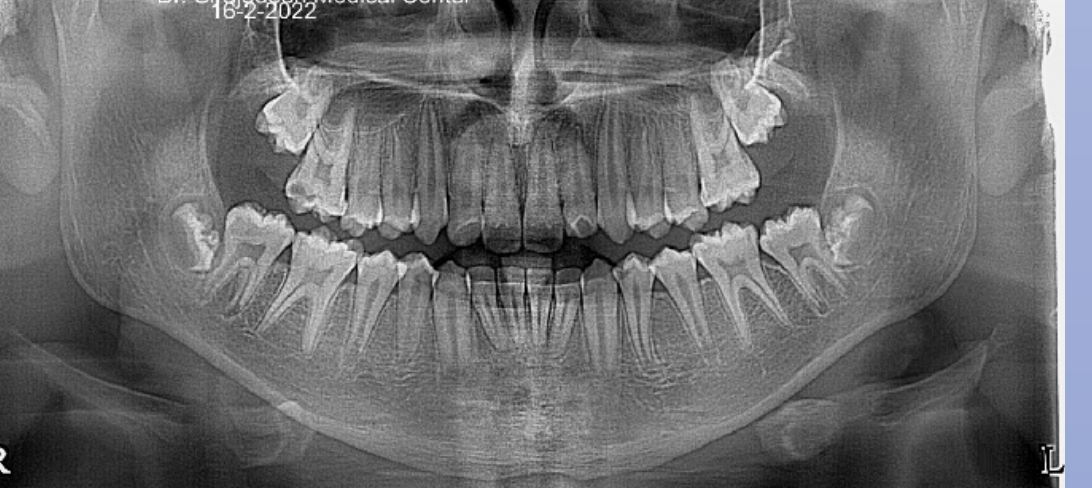

Dental age 12 is characterized by eruption of maxillary canine and the maxillary and mandibular second premolars.

Teeth erupted– Maxilla 1234567, Mandible 1234567

Teeth unerupted – all 2nd and 3rd molars

Dental age 15, the roots of all permanent teeth except the third molars are

complete, and crown formation of third molars

Dental age 21, all of the roots and molars are fully erupted